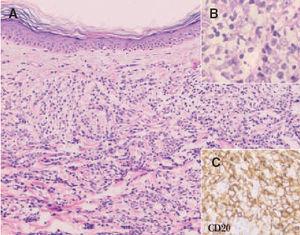

Histológicamente se observa un predominio de centroblastos e inmunoblastos. Aquellos casos que presentan una población celular homogénea de inmunoblastos (nucléolo prominente) se pueden sub-clasificar como linfomas B inmunoblásticos (fig. 9). Las células expresan habitualmente los antígenos CD19, CD20, CD22 y CD79a (antígenos pan-B). La expresión de CD5 y CD10 no es constante, y ocasionalmente pueden expresar inmunoglobulinas citoplasmáticas o de superficie. Es frecuente observar una expresión marcada de la proteína BCL-2. Puede detectarse reordenamiento clonal del gen de la IgH. Sin embargo, la expresión de BCL-2 no se relaciona con la presencia de la t(14;18)44 .

Fig. 9. A) Infiltrado difuso dérmico por células neoplásicas de gran tamaño correspondiente a un linfoma cutáneo B de células grandes de las piernas. (Hematoxilina-eosina, ×100.) B) Detalle de la marcada atipia celular. (Hematoxilina-eosina, ×200.) C) Expresión de CD20 indicando que se trata de células de estirpe B (CD20, ×200).